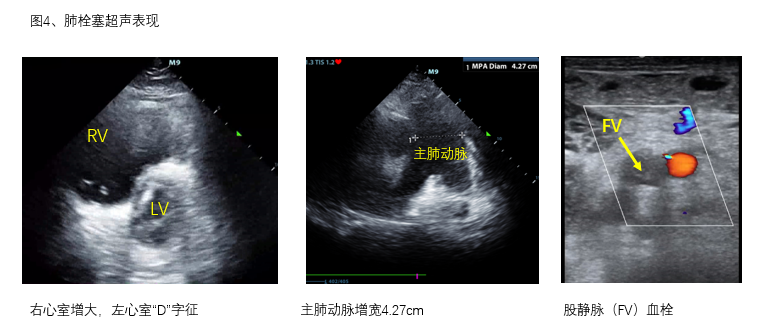

B、心腔大小 主要观察左右心比例,右心室内径与左心室内径比值。心腔均明显变小,甚至出现“kiss sign”等超声表现,需评估患者容量状态,在实施ECMO前做好容量准备,以免上机运行后出现干抽、抖管等情况。若右室舒张末内径大于左室舒张末内径者,结合临床并寻找其他直接或间接导致右心压力增加的证据和原因(图4)。当某一腔室异常增大时,需留意此腔室相关瓣膜功能,并对瓣膜功能进行简单超声评估。

E、肺动脉 发现右心增大、三尖瓣反流等疑似右心室后负荷增加的证据者,需额外观察肺动脉主干直径、有无血栓,观察肺动脉血流及测量肺动脉瓣反流血流速度等指标,寻找肺栓塞等梗阻性休克证据(图4)。